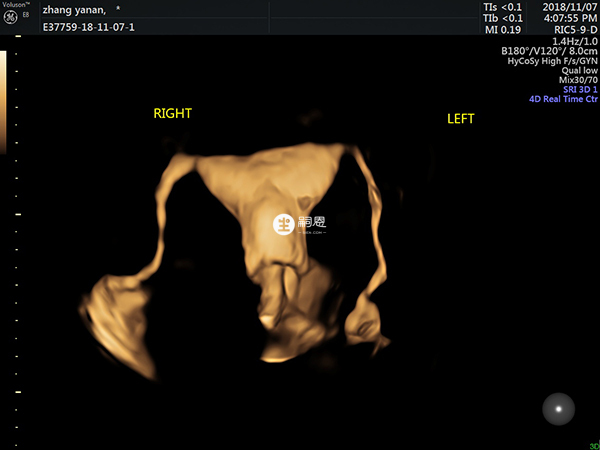

影像学检查:阴道和腹部B型超声检查能够确定巧克力囊肿的位置、大小、形状和囊内容物。